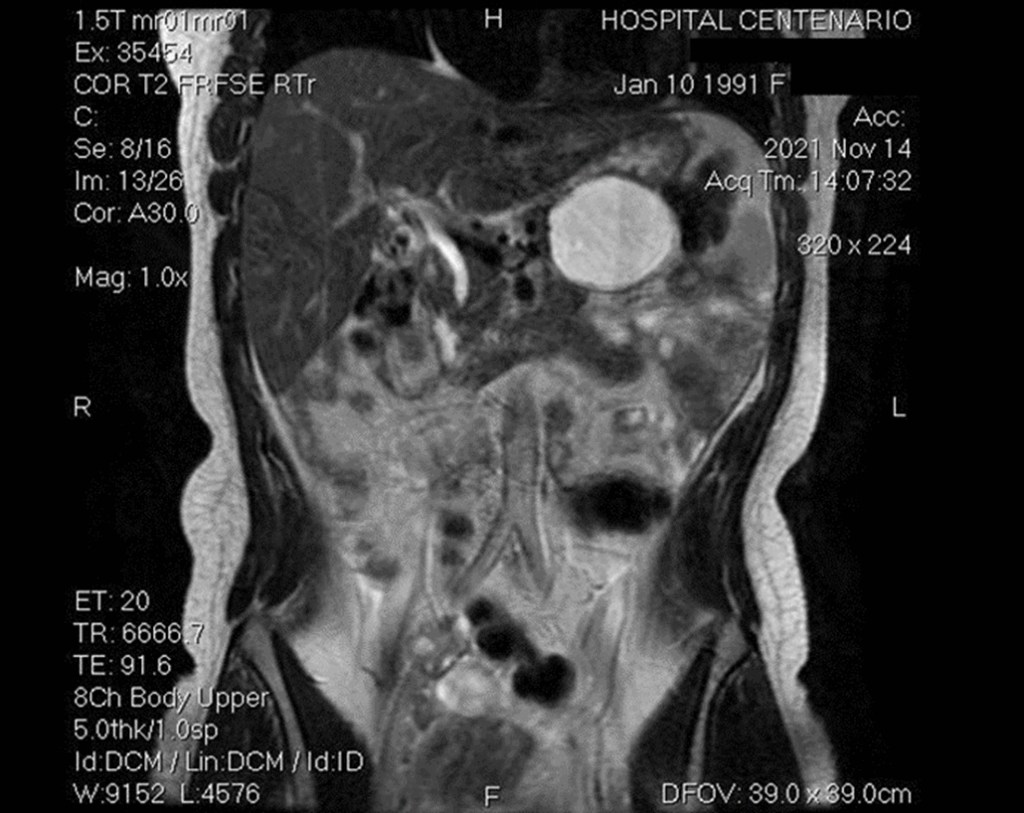

Al momento del estudio la paciente se encontraba asintomática y al examen físico no mostraba alteraciones. La TAC reveló una voluminosa formación quística de 6 x 6 cm que ocupaba la región corporocaudal del páncreas. La lesión era hiperintensa en T1 y T2 (Fig. 1). Tras la administración de contraste EV y con técnicas de sustracción, se observó sutil realce periférico, no identificándose refuerzo intraquístico ni nódulos murales. Dicha lesión en las secuencias de colangioresonancia no evidenció dependencias o conexiones con el conducto de Wirsung, el cual presentaba calibre luminal preservado. Ante dichos hallazgos, el Servicio de Cirugía del Hospital Provincial del Centenario decidió efectuar tratamiento quirúrgico.

Figura 1. TAC de abdomen – Corte coronal.